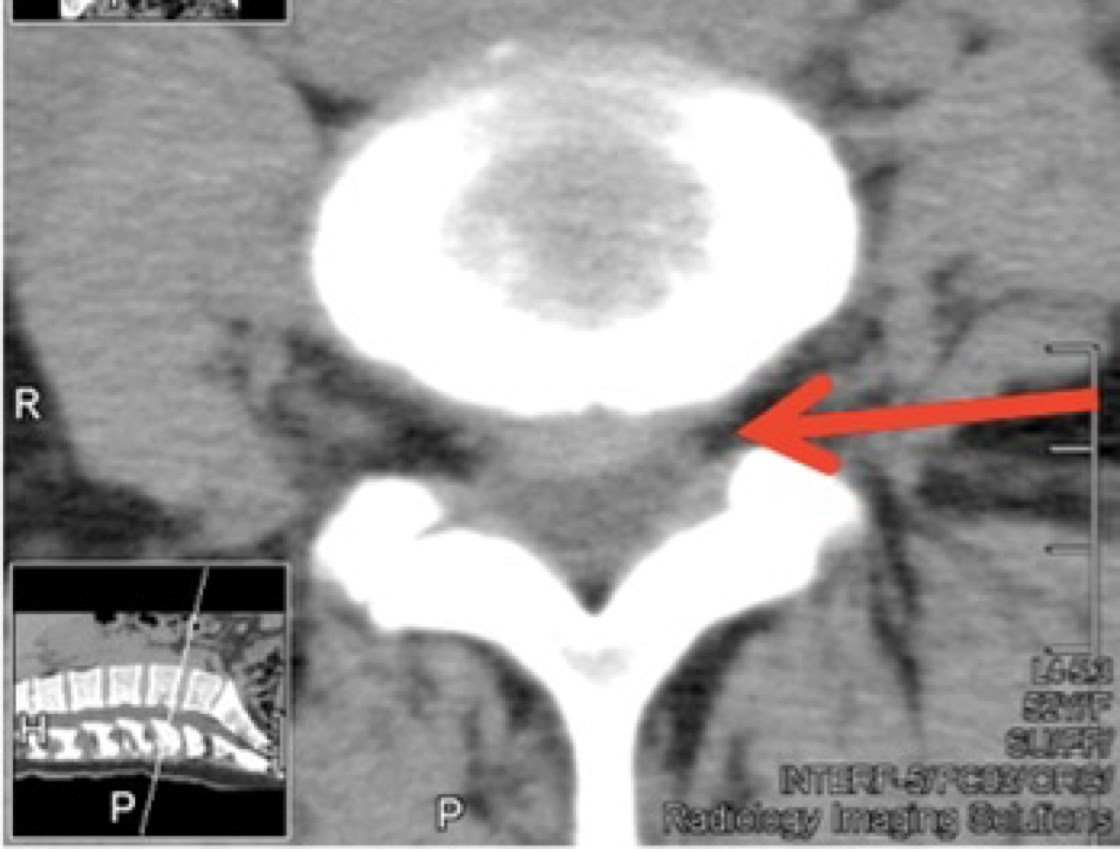

CT was ordered and shown Spinal Canal Stenosis at L4 5, and a left-sided disc prolapse with impingement of the left L4 root.